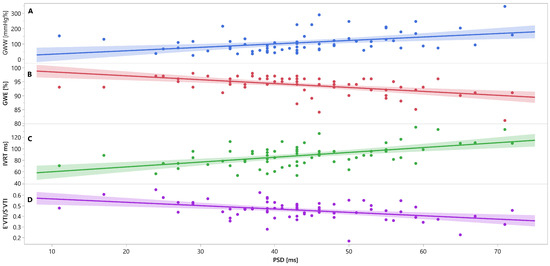

Mutual associations between PSD, GWW, GWE, IVRT and E′VTI/S′VTI are additionally shown in Figure 3, Figure 4 and Figure 5 as linear regressions.

Figure 3.

Linear regression lines for associations between PSD and GWW (panel A, line and points in blue), GWE (panel B, line and points in red), IVRT (panel C, line and points in green), and E′VTI/S′VTI (panel D, line and points in purplein healthy people. Abbreviations: E′VTI/S′VTI—systolic–diastolic coupling, GWW—global wasted work, GWE—global work efficiency, IVRT—isovolumetric relaxation time, PSD—peak systolic dispersion.